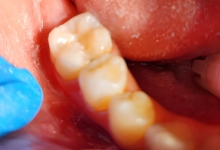

Clinica LUY ESTHETIC ART defineste parodontoza ca fiind rezultatul direct al placii dentare, care se depune pe suprafata dintilor, dar si in apropiere de marginea gingivala. Aceasta boala duce la pierderea dintilor, chiar daca ei sunt aparent sanatosi si nu prezinta carii. Edentatiile, afecteaza vorbirea, aspectul, dar si capacitatea de a mesteca.

Boala parodontala are un caracter progresiv. Pentru cazurile mai grave, recomandam tratamentul parodontal chirurgical rezectiv sau regenerativ.

O igiena bucala necorespunzatoare, fumatul, placa bacteriana si alte boli generale, permit bacteriilor sa se dezvolte in cavitatea bucala.